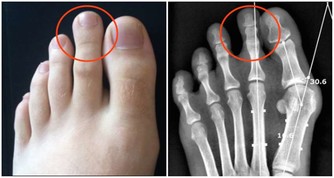

3. 去除痛風

小蘇打泡腳能消除痛風,尤其是上了年紀的人容易出現痛風,用2勺蘇打倒入溫水中,浸泡20分鐘,連續一周就能改善。